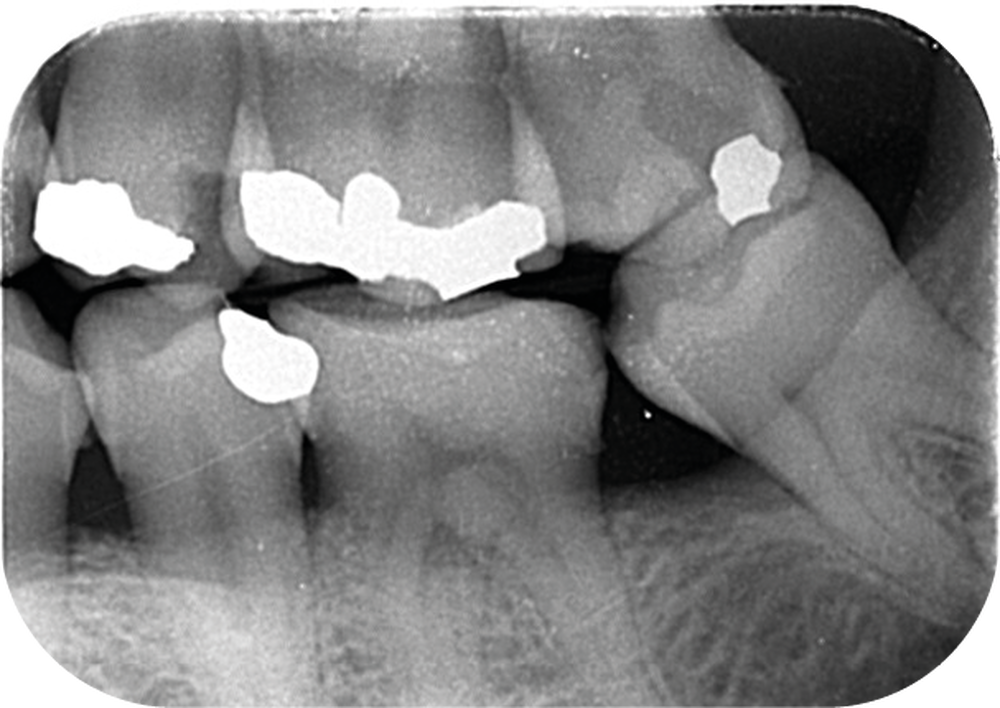

Cette version, quand elle se produit, modifie les espaces interdentaires et complique l’hygiène proximale des patients. Des caries peuvent alors se développer en interproximal sans que cela soit forcément visible à l’examen visuel (fig. 3 et 4). Les radios de type bite-wing (rétro-coronaires) prennent alors tout leur sens (fig. 5 et 6).